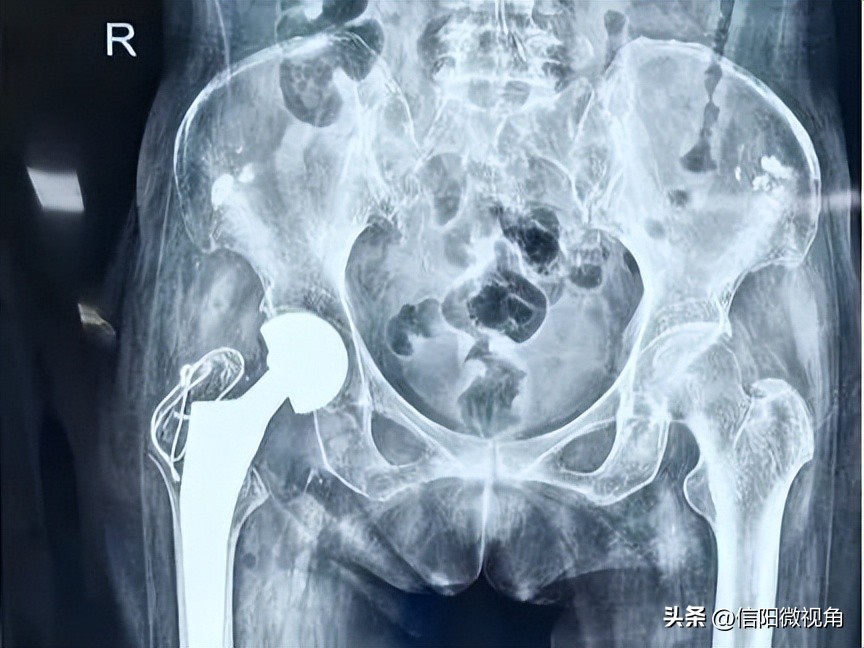

在多学科专家的保驾护航下,经过全面细致的准备,手术如期进行。由郑炎主任主刀,麻醉科周一鸣副主任医师进行麻醉指导,通过多学科的高效协作、密切配合,手术顺利完成!术中患者生命体征稳定,未出现心律失常及血压异常波动等。

术后